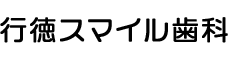

初診時の口腔内

診査の結果、金具をかけている歯がむし歯になっているため(写真黃丸)、金具のバネ(クラスプ)がしっかりと歯にかかっておらず、入れ歯が浮きやすい状態になっていました。入れ歯が浮いてしまうと、食べ物が挟まり、痛みが出てしまいます。また、入れ歯が動いてしまうので、話もしにくくなります。さらに、入れ歯が沈み込まないようにする装置(レスト)も歯に合っておらず(写真青丸)、入れ歯が過度に沈み込み、歯ぐきを傷めていました。